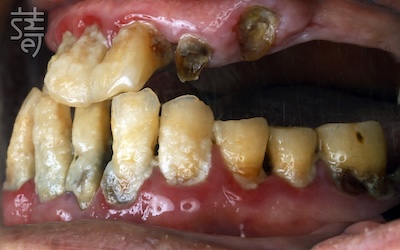

「以前覺得牙齒掉光是自然現象,就算了。」半退休的黃爸爸,靠木工、水電維生,手腳俐落卻忽略口腔健康。

上顎牙齒逐一脫落,他也不以為意,反正茹素、對許多食物過敏,煮軟就能吞。

直到有天連豆腐、燉菜吃得都痛,他才意識到問題嚴重,這場疼痛也成了他走向 All-on-5顴骨植牙重建的開端。

“I used to think losing all my teeth was just a part of getting old—something you accept,” said Mr. Huang, a semi-retired handyman who had spent his life working with wood and wiring but had long ignored his oral health. One by one, his upper teeth fell out. He paid little attention; after all, he was a vegetarian, allergic to many foods, and could manage by cooking things soft enough to swallow. But when even tofu and stewed vegetables became painful to eat, he realized something was seriously wrong. That pain marked the beginning of his journey toward All-on-5 zygomatic implant reconstruction.

一開始,女兒替黃爸爸搜尋「水雷射牙周治療」,以為治好牙周病就能保住牙齒;

但檢查發現,上顎僅剩的牙幾乎都是爛牙根,若採傳統方式不僅曠日費時,費用也十分高昂,讓他心生退意。

At first, his daughter searched for “laser periodontal therapy,” thinking that treating gum disease might save his teeth. But the exam showed that nearly all his upper teeth were nothing more than decayed roots. Traditional treatment would have been long, invasive, and prohibitively expensive.